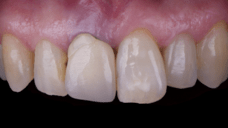

After an appropriate healing period, the definitive prosthesis was planned and delivered. A screw-retained zirconia crown was fabricated to ensure long-term durability, optimal esthetics, and retrievability. Zirconia was selected for its mechanical strength and excellent esthetic properties, blending seamlessly with the adjacent natural dentition in both form and color.

The final crown was designed to maintain the gingival architecture that had been shaped by the provisional. Special attention was paid to the emergence profile, contact points, and translucency to achieve harmony with the patient’s smile. The definitive restoration provided functional stability and esthetic integration, fulfilling the patient’s expectations for a fixed and natural solution.